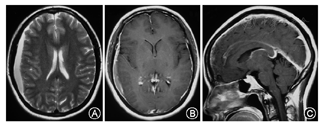

SIH患者2例头MR平扫结果正常,1例患者既往有高血压病史,头MRI显示侧脑室周围脱髓鞘样改变,余未见异常。SIH头MRI异常表现包括:脑叶出血、硬膜下血肿、脑静脉窦血栓、小脑扁桃体下位、蛛网膜下腔出血、脑室变小、垂体充血、脑静脉窦扩张、弥漫性硬脑膜强化。

(1)病例1:女,37岁,因"头痛1个月"入院。表现为后颈枕部钝痛,向肩胛部放射伴恶心、耳鸣,躺下后10 min可缓解。病后第2天头CT正常。病后第3天头MRI正常。查体:四肢腱反射活跃-亢进,余神经系统查体(-)。病后第5天腰椎穿刺,压力35 mmH2O,白细胞10×106/L,蛋白0.74 g/L,糖、氯化物正常。病后1个月头CT:右侧颞、顶、额部硬膜下血肿;小脑幕增宽,考虑硬膜下血肿。病后41 d头MRI平扫+增强:右侧额顶颞叶亚急性晚期硬膜下血肿;左侧颞、顶、枕部、双侧小脑幕上硬膜下少量出血;小脑扁桃体下位;弥漫性硬脑膜强化(图1)。颈胸腰椎增强MRI正常。(2)病例2:男,53岁,因"头痛3 d"入院。表现为前额部胀痛,伴后颈背部疼痛,躺下休息可缓解。神经系统查体(-)。病后3 d时腰穿,压力50 mmH2O,脑脊液白细胞6×106/L,蛋白0.65 g/L,糖、氯化物正常。起病当天头CT正常。发病第7天头MRI平扫+增强:硬脑膜、小脑幕异常增厚强化(图2)。头MRV、颈胸腰椎增强MRI正常。(3)病例3:女,39岁,因"头痛20 d,左侧肢体无力5 d"入院。表现为全头搏动性胀痛,平卧位减轻,坐起后加重,伴头晕、头鸣、耳鸣、颈部僵硬感。发病第4天头CT正常。第13天、18天各出现一次癫痫大发作,持续约1 min。第13天时头MRI正常。第15天突发右侧肢体无力,查体:右上肢肌力4级,右下肢0级,右侧Babinski征、Chaddock征(+),颈抵抗(+)。腰穿测不出压力。第19天复查头CT示左额顶叶高密度影,提示硬膜下血肿。第21天头MRI:硬膜下血肿吸收明显,遗留左侧额叶皮质下片状长T2信号。全脑DSA检查正常。(4)病例4:男,44岁,因"头痛半个月"就诊。头顶及颈部持续胀痛,坐起或站立时明显,平卧位可减轻。发病第4天头CT:未见异常。腰穿压力20 mmH2O,白细胞0,蛋白0.8 g/L,糖、氯化物正常。第22天头MRI增强:脑膜强化、脑室缩小。颈胸腰椎增强MRI正常。(5)病例5:女,28岁,因"头痛4 d"就诊。头痛位于头顶及后颈背部,胀痛,平卧时减轻,站立时加重难以忍受,伴头晕、恶心、呕吐。查体:颈抵抗3横指。腰穿压力30 mmH2O,白细胞6×106/L,蛋白1.3 g/L,糖、氯化物正常。发病第2天头CT正常。半个月时头MRI:垂体饱满。头MRA 、MRV和颈椎MRI正常。

SIH在MRI上主要表现为硬脑膜弥漫性增强、硬膜下积液或出血、垂体增大、静脉窦扩张、脑室变小以及小脑扁桃体向下移位等[3,7]。20%的患者不出现硬脑膜强化或其他任何MRI异常表现[7]。本文中五例典型患者MRI表现涵盖了SIH大部分MRI特点。SIH的头MRI存在动态演变过程,病程初期MRI结果正常,可以在病程中发生变化,本研究中病例1和3患者的头MRI均存在动态演变过程。